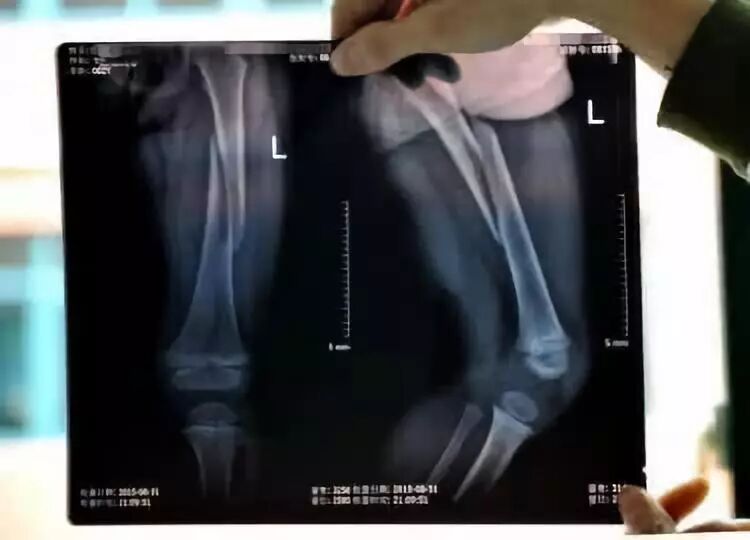

10月12日,240斤的蔡鹏因为学直播平台上很火的跳蹦床动作,不慎造成膝盖髌骨脱位。

到达现场的郑子兰急救小组经过检查,发现蔡鹏的右膝明显活动受限,疼痛明显,医生想把他从蹦床上挪到外面都做不到。为避免造成二次损伤,医生在晃动的蹦床上,用夹板给蔡鹏右下肢做了外固定。

“患者体重较大,跳高后落下,冲击力较大;蹦床非常软,他站立时重心不稳摔倒,最终造成髌骨脱位。”沈阳市骨科医院医生表示,蹦床运动看似简单,但是跳不好,容易造成骨关节扭伤。